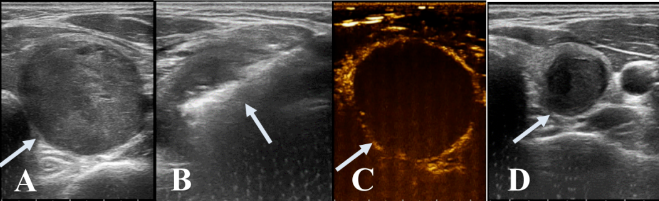

精准消融:在超声引导下,将消融针精准插入结节内,启动消融程序,使结节区域产生高温灭活肿瘤细胞;

术后评估:消融术后即刻进行超声造影检查,确认结节已完全消融;术后三个月复查,观察结节体积明显缩小。